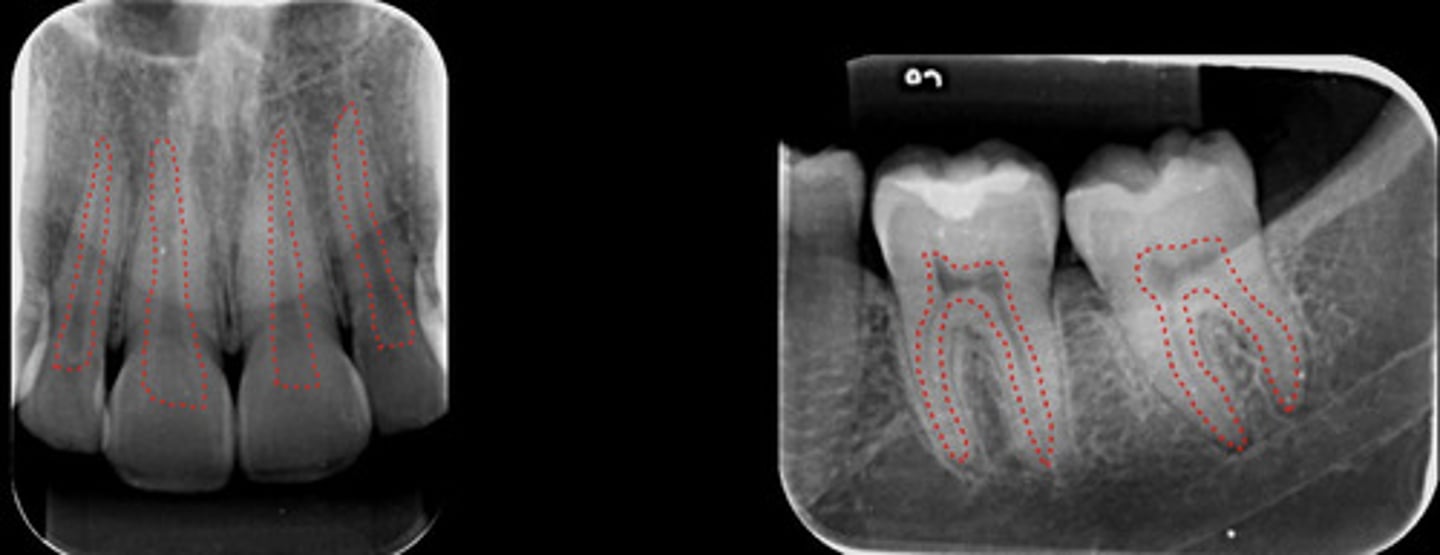

Pulp chamber and root canals

What are the dotted lines representing?

periodontal ligament space